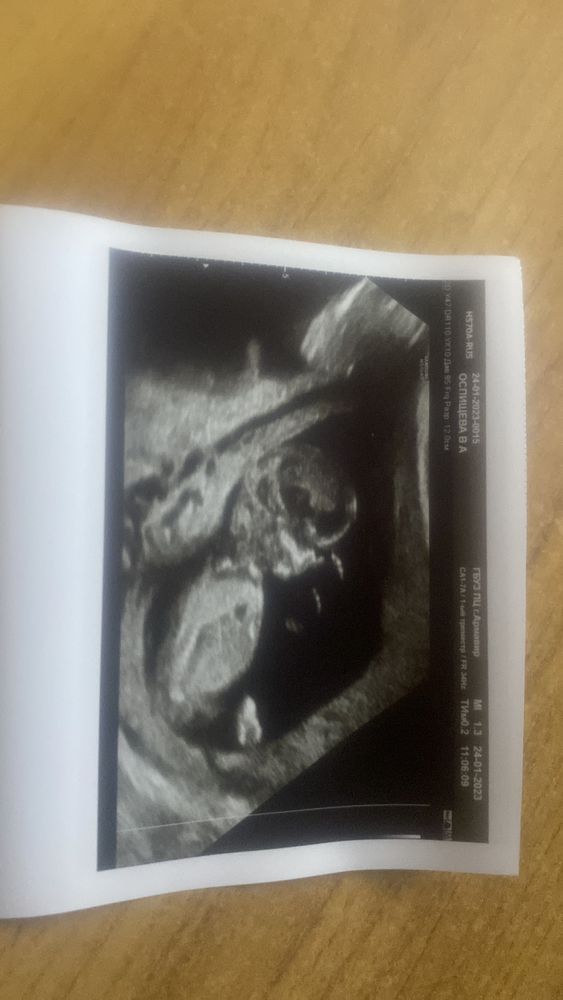

Приветик всем☺️. Сегодня был первый скрининг, и 4 узи , и опять другой срок ставят 😂. Было 12.3, сегодня по узи поставили 13.1

Предлежания нет, расположен по передней стенке. ЧСС 158

К сожалению рассмотреть что между ног не смогла 😂 , крутился от узи как мог. Она его и так ловила , и так, на доли секунды показал и спрятал 😂Сказала хочешь приди через пару недель. Надеюсь что значек не удачу🤭не придется менять

Дальше прикреплю фото, может интуитивно кто скажет